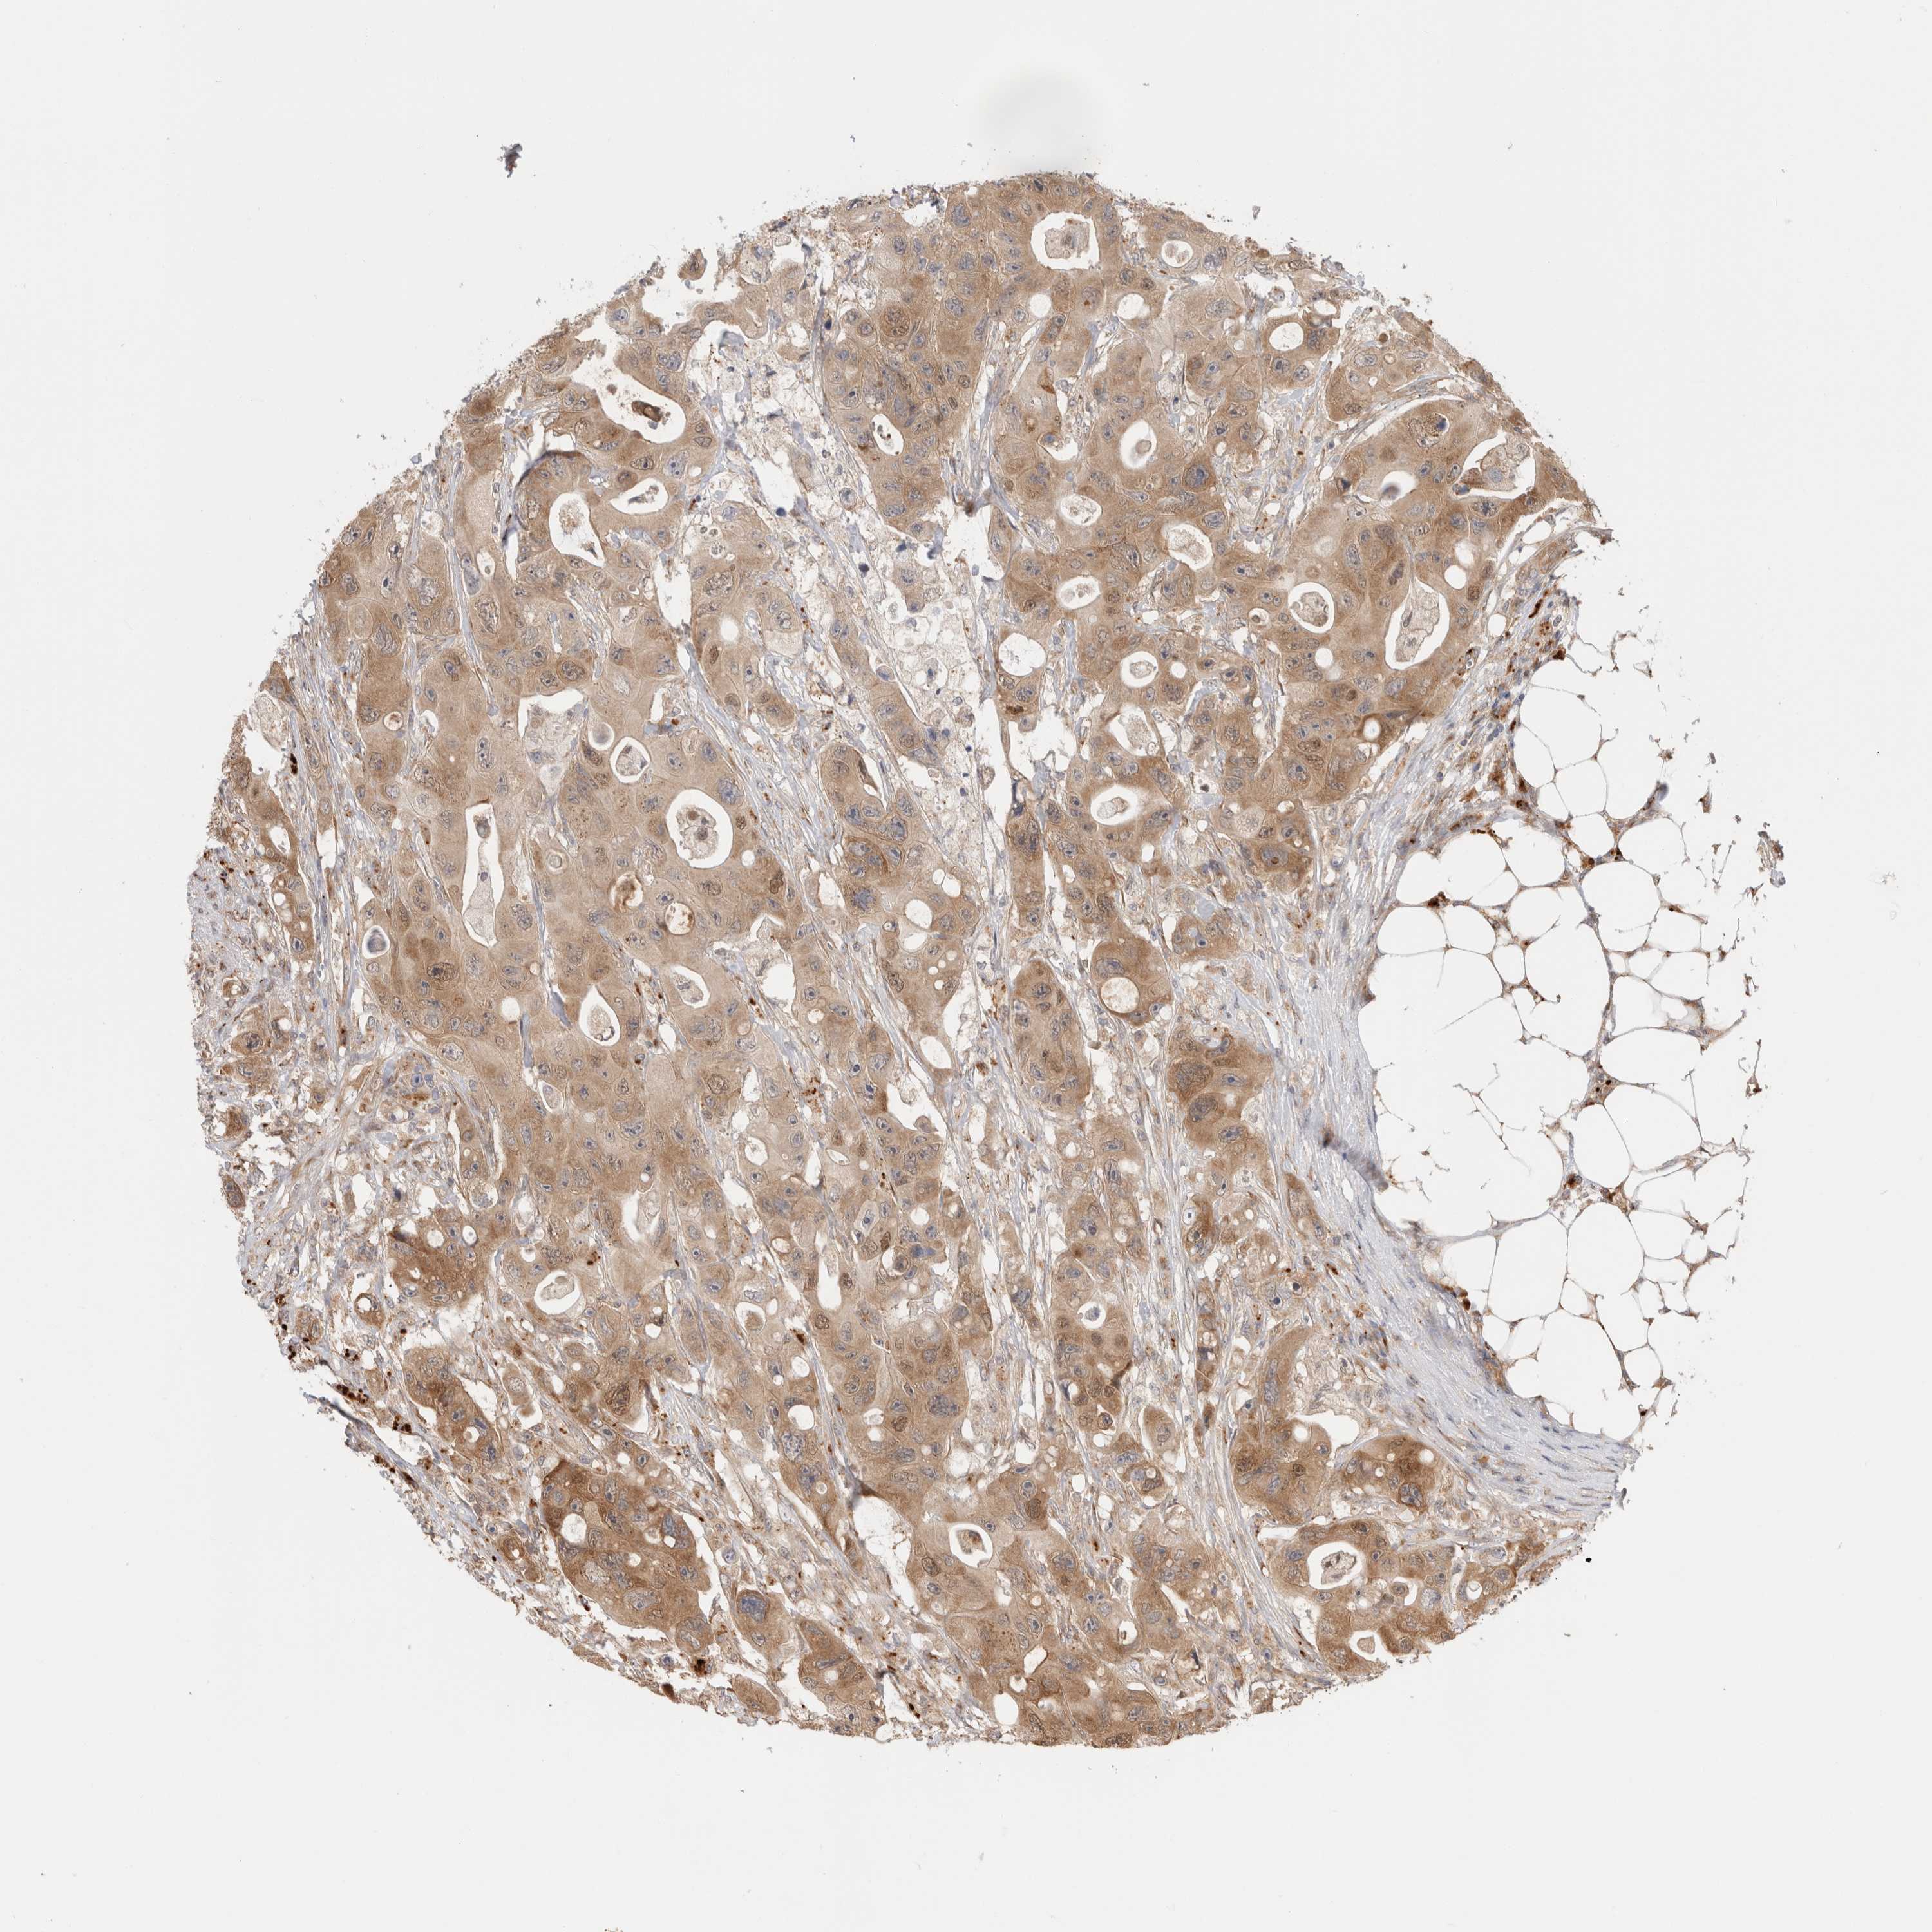

CANCER COLORECTAL CANCER Show tissue menu

Colorectal cancer

Colon adenocarcinoma